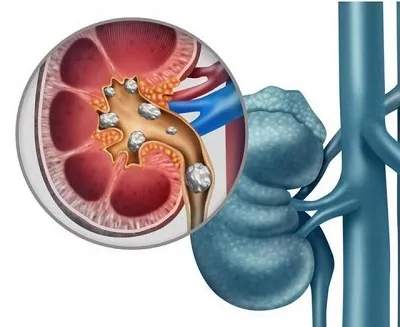

痛风性肾病是由于血尿酸产生过多或排泄减少形成高尿酸血症所致的肾损害,属于痛风病的一种。该病临床表现可有尿酸结石、小分子蛋白尿、水肿、夜尿、高血压、血尿酸升高及肾小管功能损害。以北方人多见,无明显的季节性,肥胖、喜肉食及酗酒者发病率高。

临床表现可有显着的高血压和氮质血症,在病程中有25%病人会夹杂尿路感染,一般来说痛风肾多在不知不觉中发病,而且进展很缓慢,常经历10~20年才发生肾衰。还有约20%的病人并发尿酸性结石,可出现肾绞痛、血尿或尿中排出尿酸石。

以上就是关于痛风性肾病的三个不同发展时期的表现的介绍,痛风性肾病属于痛风病的一种,因此患者除了严格遵守痛风病人的膳食原则、增加饮水量、碱化尿液等措施之外,加强清热利尿,通淋消石,对消除因尿酸盐沉积于肾小管及肾间质引起的炎症反应和因尿酸结晶沉积引起的尿路阻塞有一定的治疗作用。患者在进行治疗的时候,一定要选择正规的医院进行专科诊断检查,查明病情发展情况,以便进行针对性的治疗。